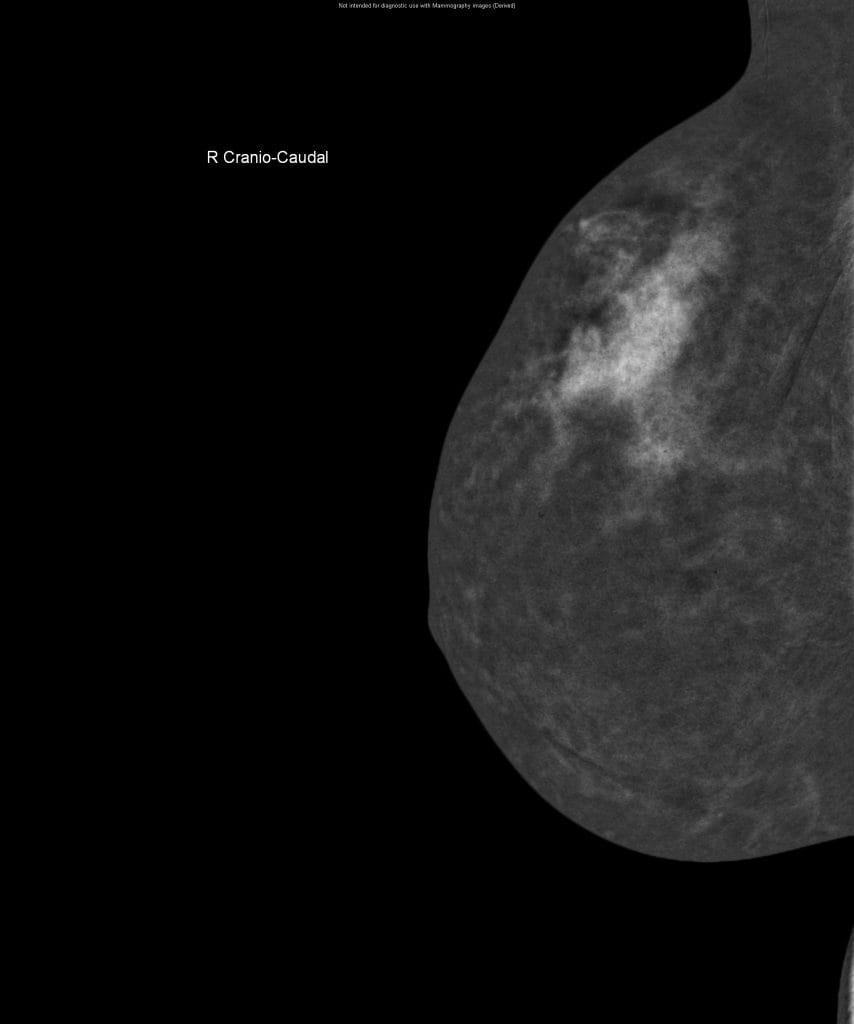

CESM is an advanced form of mammography that uses a safe dye injected into the bloodstream. This dye highlights areas of concern within the breast, giving clinicians a much clearer and more detailed image than a traditional mammogram.

“Sometimes it can be difficult to interpret a mammogram, especially in patients with dense breast tissue”, Nicole explains. “It’s a bit like looking for a cloud in a sky full of clouds. The contrast helps remove that ‘noise’ and shows us exactly what’s going on inside the breast.”